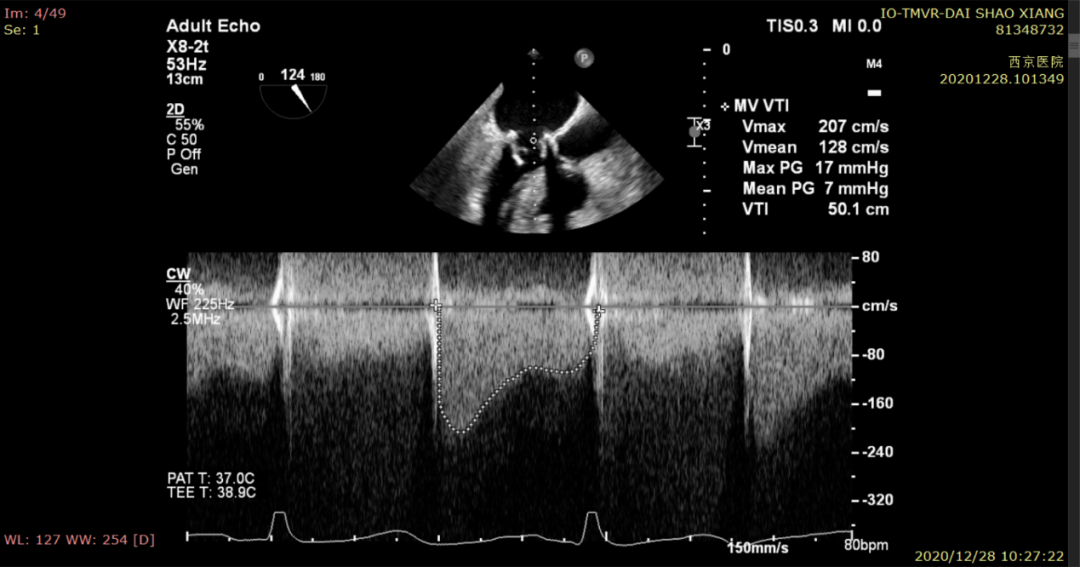

患者,女,72岁,因“二尖瓣生物瓣置换术后11年,间歇性胸闷、气短半年,加重3月”入院就诊。患者于11年前因二尖瓣关闭不全,行二尖瓣生物瓣置换术,植入爱德华27规格的外科生物瓣膜。半年前无明显诱因感气短、胸闷,不能平卧,休息后缓解,未予特殊处理,其后症状逐渐加重,至西京医院就诊。行超声心动图检查提示:左心室,射血分数(EF)67%,二尖瓣位生物瓣位置正常,瓣膜略增厚,测得二尖瓣生物瓣有效瓣口面积约2.5cm2,瓣下血流速度加快(Vmax=207cm/s),平均跨瓣压差达7mmHg,瓣上可见大量返流,二尖瓣生物瓣关闭不全伴狭窄(轻度)并后内侧瓣叶脱垂及钙化;三尖瓣可见少至中量返流,肺动脉高压(收缩压)约为62mmHg。